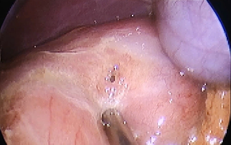

Cứu người bị áp xe ổ bụng hiếm gặp do mắc xương cá

Tin nóng y tế - 09/10/2025 20:05SKĐS - Chiều 9/10, Bệnh viện Lê Văn Việt (TPHCM) cho hay, các bác sĩ khoa Ngoại Tổng hợp vừa phẫu thuật thành công một ca áp xe ổ bụng do dị vật xương cá có thể nguy hiểm đến tính mạng nếu chậm trễ xử trí.